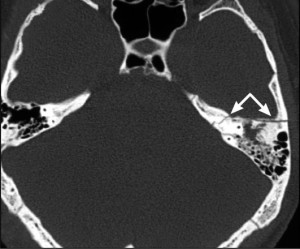

При получении человеком травмы в области виска, важно своевременно и правильно поставить диагноз. Для этого доктору необходимо видеть полную рентгенологическую картину ситуации. К сожалению, рентгеновские снимки далеко не всегда позволяют правильно увидеть линию перелома пирамиды и оценить серьезность заболевания.

Очень часто в таких случаях назначается КТ височных костей или рентген в дополнительных проекциях (медиальной, боковой, косой). Так же может потребоваться консультация ЛОР-врача или невролога.

При травматических поражениях очень важно, как можно скорее поставить диагноз и назначить лечение. От этого порой зависит, сможет ли человек полностью побороть свою болезнь. Самым информативным и быстрым методом исследования является КТ височных костей. Данное исследование позволяет максимально быстро определить степень поражения. Так же часто назначается МРТ.

КТ височных костей и МРТ позволяет определить различные опухоли, травматические повреждения, а также отиты, абсцессы и дегенеративные влияния. Стоит отметить, что при необходимости повторных исследований КТ височных костей не назначают, так как рентгеновское излучение в области головного мозга и так не желательно.

Клинически перелом проявляется односторонним снижением слуха, заушной гематомой, истечением крови и/или ликвора из слухового прохода. Для диагностики проводят КТ височной кости, аудиометрию, неврологический осмотр и электронейрографию.